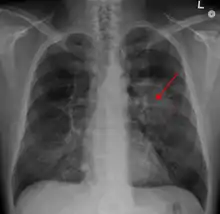

![]() | |

| A chest X-ray showing a tumor in the lung (marked by arrow) | |

A person suspected of having lung cancer will have imaging tests done to evaluate the presence, extent, and location of tumors. First, many primary care providers perform a chest X-ray to look for a mass inside the lung.[8] The X-ray may reveal an obvious mass, the widening of the mediastinum (suggestive of spread to lymph nodes there), atelectasis (lung collapse), consolidation (pneumonia), or pleural effusion;[9] however, some lung tumors are not visible by X-ray.[5] Next, many undergo computed tomography (CT) scanning, which can reveal the sizes and locations of tumors.[8][10]